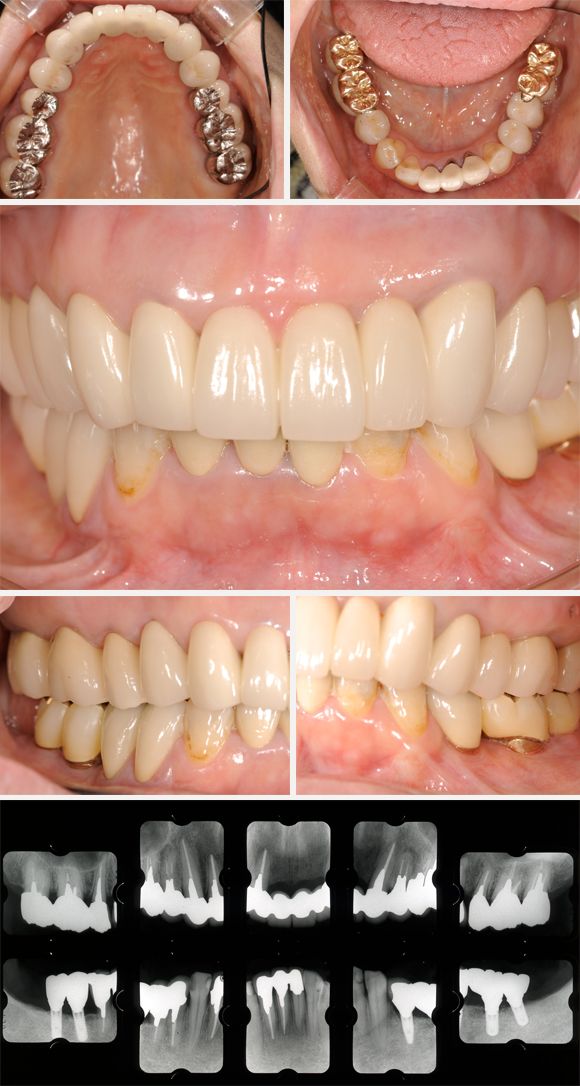

全顎治療費用

3,870,000円(税別)